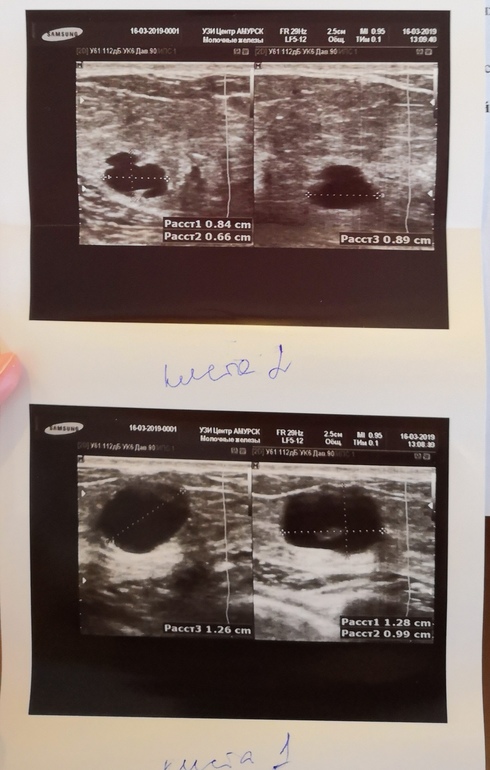

Недели 3 назад нащупала горошину в груди, гулящую, вообще не беспокоит вроде, но было пару раз ощущения побаливания, пострелывания. В общем записалась я к маммологу на 20 марта, а тем временем сделала УЗИ молочных желез. Узистка увидела 2 кисты, сказала ничего страшного, сказала проконсультироваться у маммолога.

Пугает вторая киста - непонятной, неправильной, формы с врастаниями во внутрь самой кисты - на фото видно.